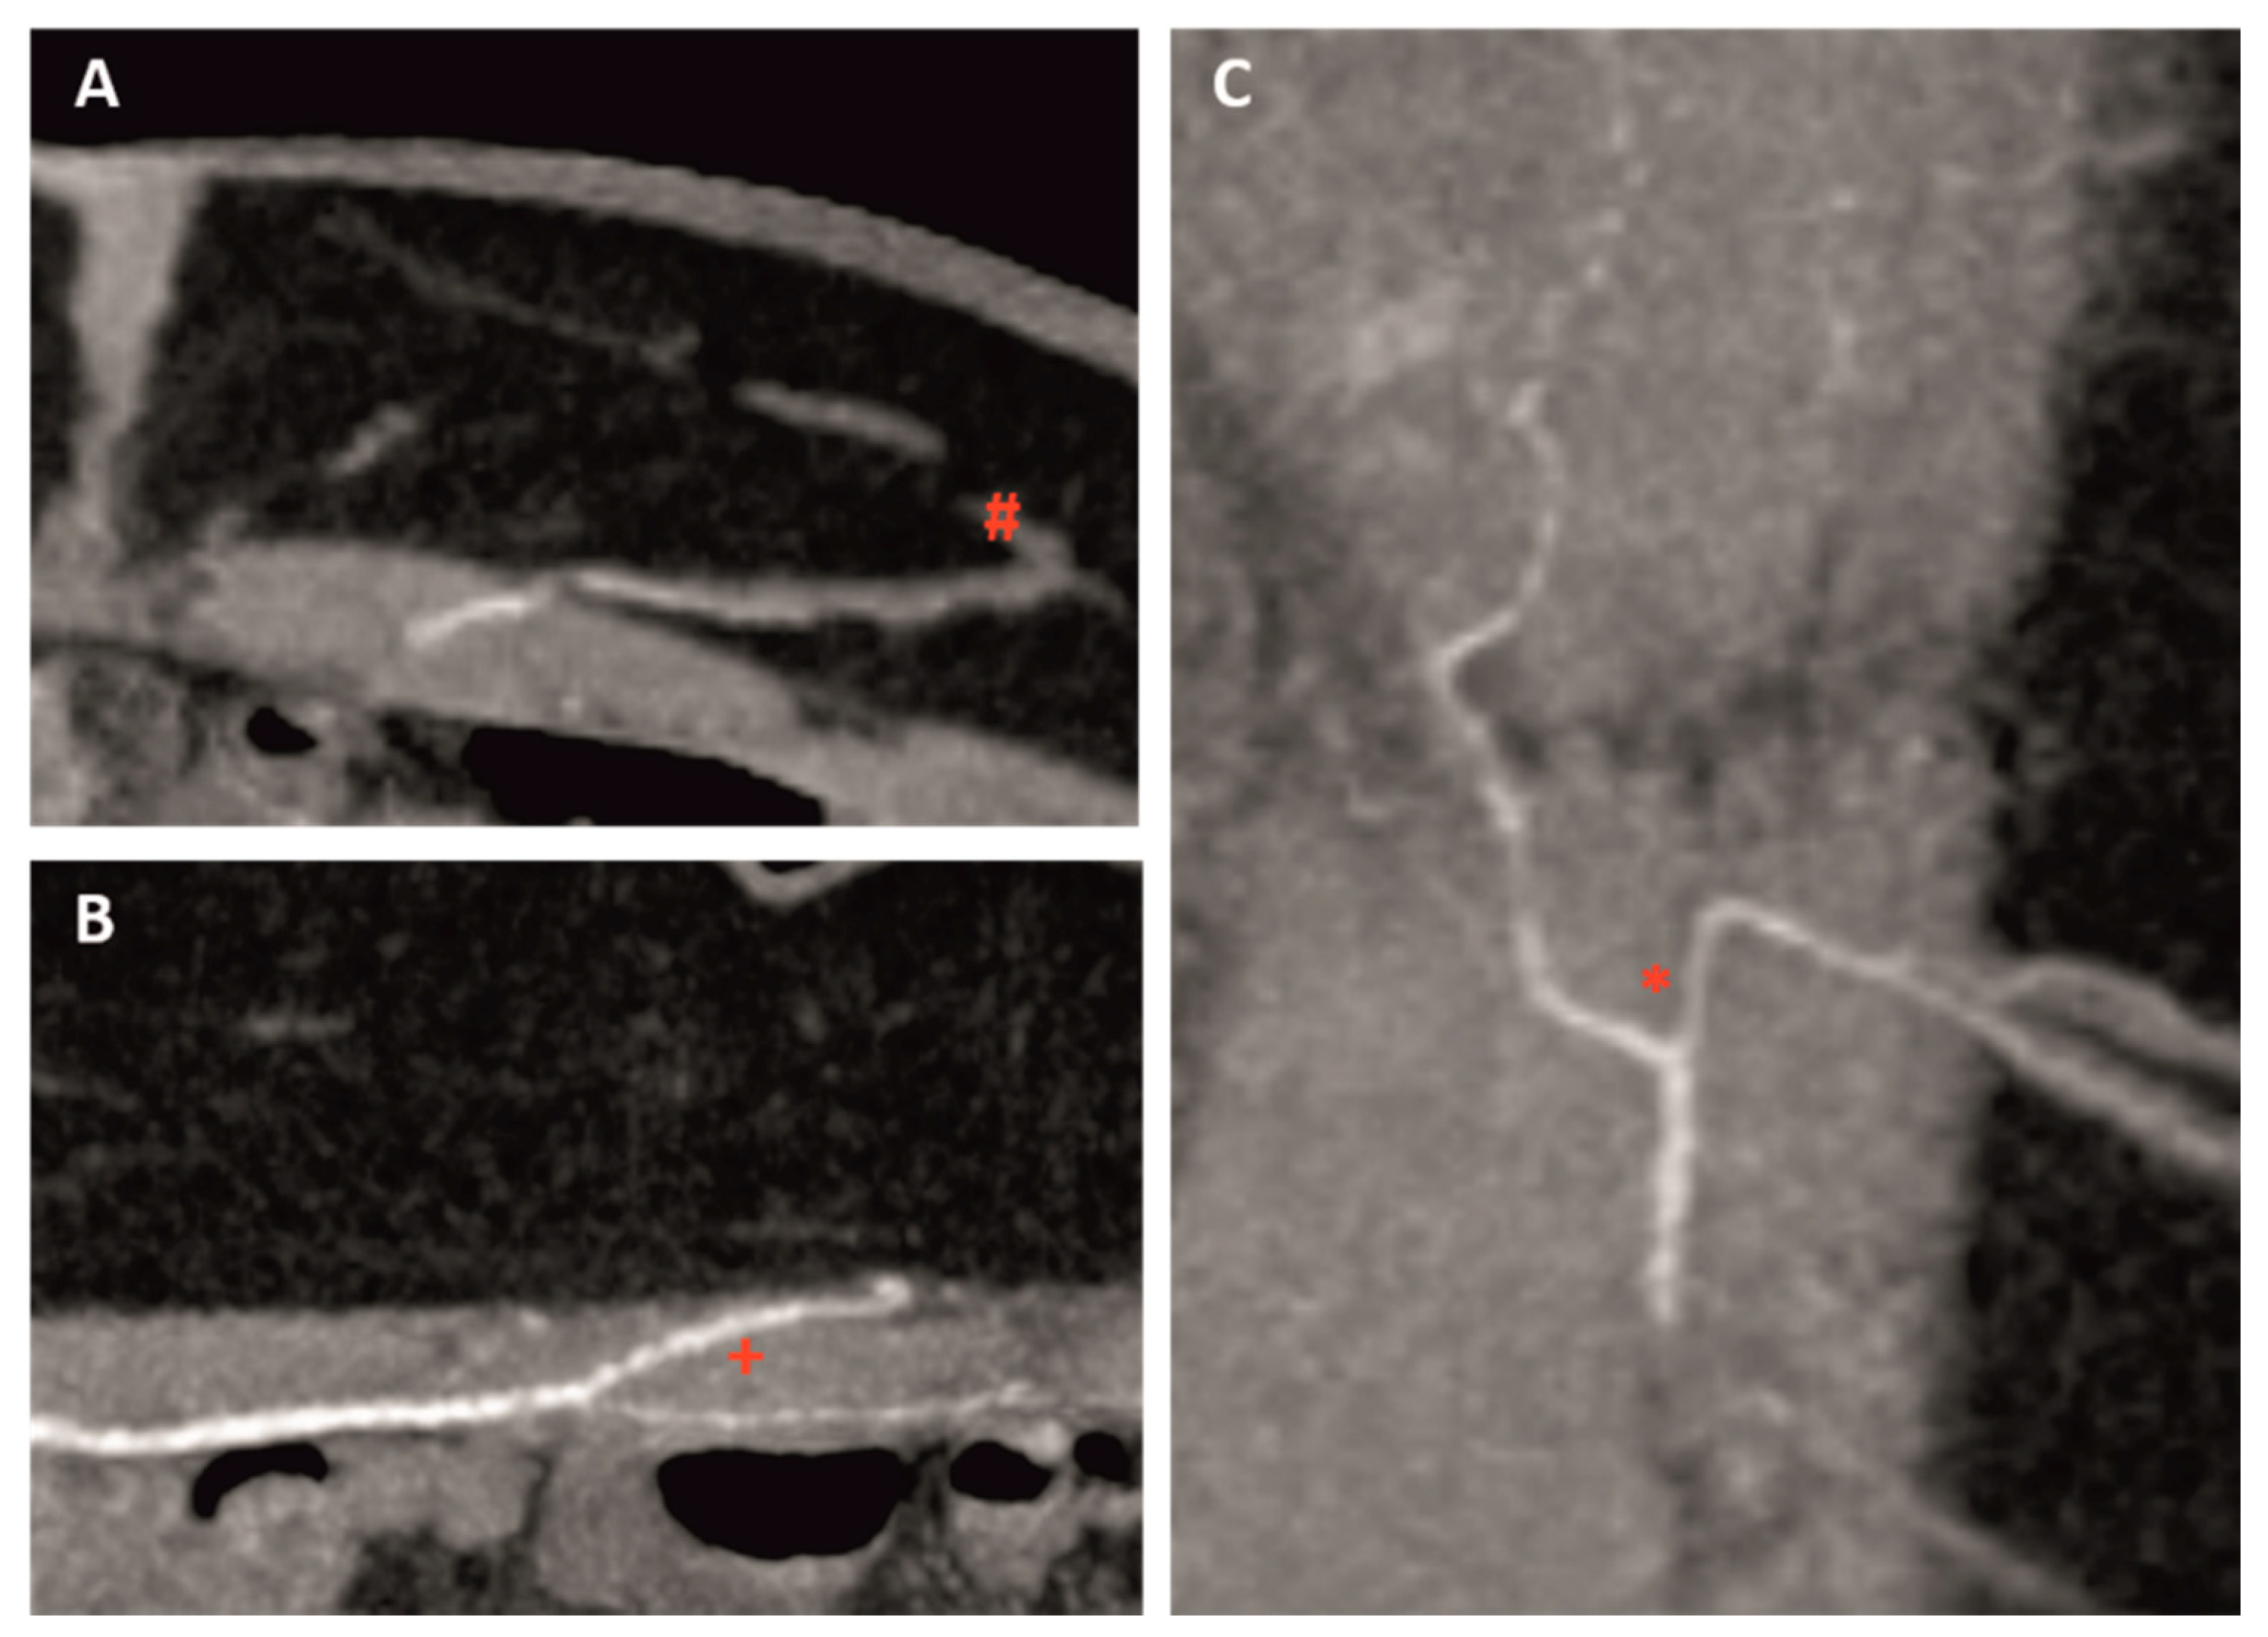

| Intramuscular course | Short (<1.5 cm), long (>1.5 cm), no intramuscular course (medially around the rectus muscle) |